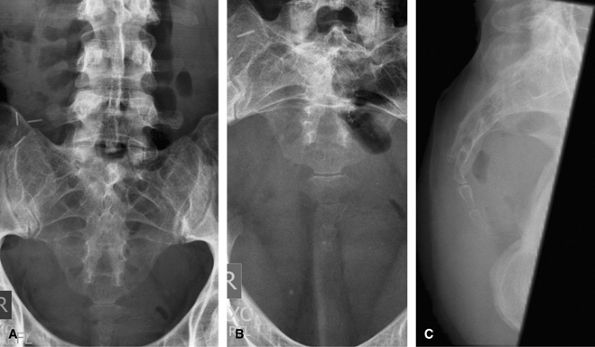

Sacroiliac Joints

Good initial screening test for sacroiliitis. MRI is more sensitive and saves radiation to the gonads.

![]() |

Figure 40 (A) AP pelvis. (B) AP oblique of right sacroiliac joint. (C) AP oblique of left sacroiliac joint.